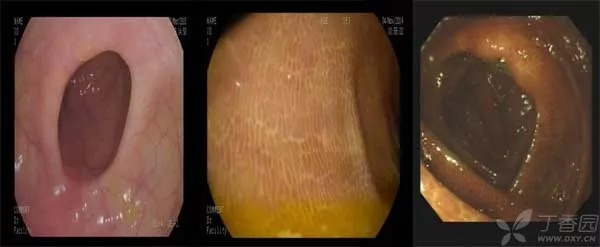

此外,这些药还可能会使色素沉着于肠壁,出现结肠黑变病,就是像下图这样的变化:

图片来源:丁香园